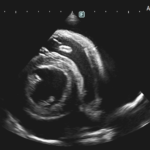

高齢(12歳)のアフガンハウンドが吐きたそうだけど、何も出てこない。次第に起立出来なくなったとのことで夜間に救急で来院しました。症状とエックス線検査から胃捻転と診断しました。また聴診時に心音は遠く、聴取出来ませんでした。胸部エックス線検査においてムーンハートが確認されました。超音波ガイドで出血性心のう水を2リットル抜去しました。バイタルサインが落ち着いたところで胃捻転整復術を実施しました。その後も出血性心のう水は貯留傾向にありました。高齢であることから血管肉腫が疑われましたが、各種画像診断においても腫瘤の存在はなくまた細胞診においても血管肉腫の可能性は低いものと判断しました。胃捻転から2週間後、心膜の生検と再発性の心膜貯留を回避する目的で心膜切除術を実施しました。心膜は顕著に肥厚し、線維化を伴っていました。病理検査の結果をもとに内科療法を併用する予定です。高齢ながら頑張ってくれました。